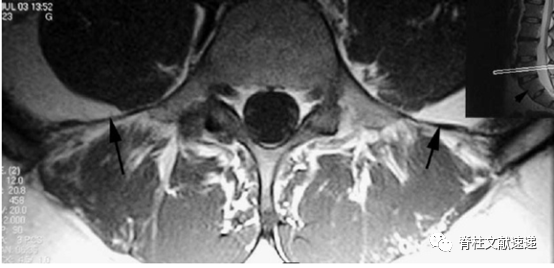

Hughes RJ等人的研究中提出,通过在MRI上识别髂腰韧带来确定椎体节段,因髂腰韧带起自L5横突。MRI上可以清除的看到髂腰韧带为L5横突延伸至髂后内侧嵴的单或双低信号带,如图6所示,当髂腰韧带出现在移行椎头侧椎体时,移行椎被认定为S1。如图7所示,当髂腰韧带出现在移行椎水平时,移行椎被认为L5。如图8所示,当没有找到在正常的髂腰韧带时,移行椎也被认定为L5,在这种情况下,我们假定横突的增宽增大导致较小的韧带发育。

图6注:T1加权像轴向MRI结果显示髂腰韧带(大箭头)被识别在移行椎(右上图片中小箭头)头侧椎体,该椎体被认为是L5,移行椎被认为是S1。

图7注:T1加权像轴向MRI结果显示当移行椎水平识别到髂腰韧带(箭头处)时,移行椎被认为是L5。